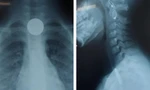

Kết quả xét nghiệm cho thấy có tình trạng tiểu cầu giảm, chỉ số cảnh báo tình trạng viêm tăng ở mức rất cao, tăng men gan, có hồng cầu và protein trong nước tiểu. Chỉ số hậu COVID-19 của bệnh nhi cao gấp 10 lần so với các chỉ số thông thường và mắc sốt xuất huyết.

Các bác sĩ đã hội chẩn và kết luận với chẩn đoán bé Q. mắc hội chứng MIS-C (viêm đa cơ quan sau mắc COVID-19) do phản ứng của cơ thể, gây tổn thương toàn bộ hệ thống cơ quan của cơ thể (gan, thận, phổi, não, huyết học). Cùng lúc gặp cả hội chứng hậu COVID-19 và mắc sốt xuất huyết khiến bệnh nhi ở mức nặng, tiên lượng xấu vì nguy cơ tăng đông máu cao, có thể dẫn đến tình trạng tắc mạch não, tắc mạch phổi, mạch vành hoặc tắc mạch máu trong cơ thể ở bất kỳ cơ quan nào.